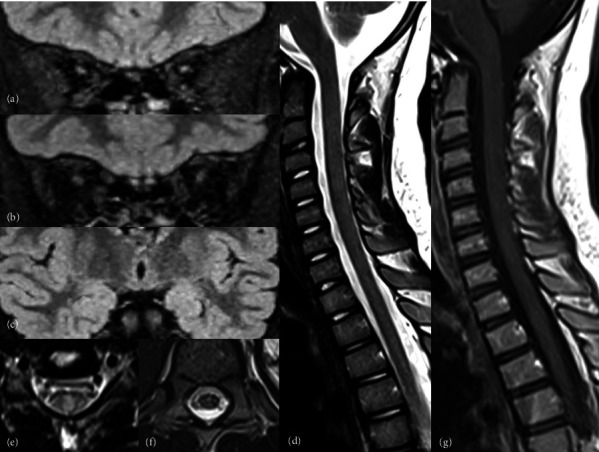

Biotinidase deficiency is a rare treatable metabolic disorder caused by biallelic mutations in the BTD gene. In the absence of neonatal screening and treatment, affected children develop typically optic atrophy, hypotonia, early onset seizures, developmental delay, and cutaneous manifestations. Some patients may have atypical presentations mimicking a demyelinating disorder of the central nervous system. We report on the first genetically confirmed Tunisian patient with biotinidase deficiency who presented initially with cutaneous manifestations misdiagnosed as dermatophytosis and subsequently with an opticospinal syndrome leading to the diagnosis of seronegative neuromyelitis optica spectrum disorder that was dramatically improved under biotin. We carry on a review of the literature of the previously reported pediatric cases with an opticospinal syndrome revealing biotinidase deficiency.

Abstract Image